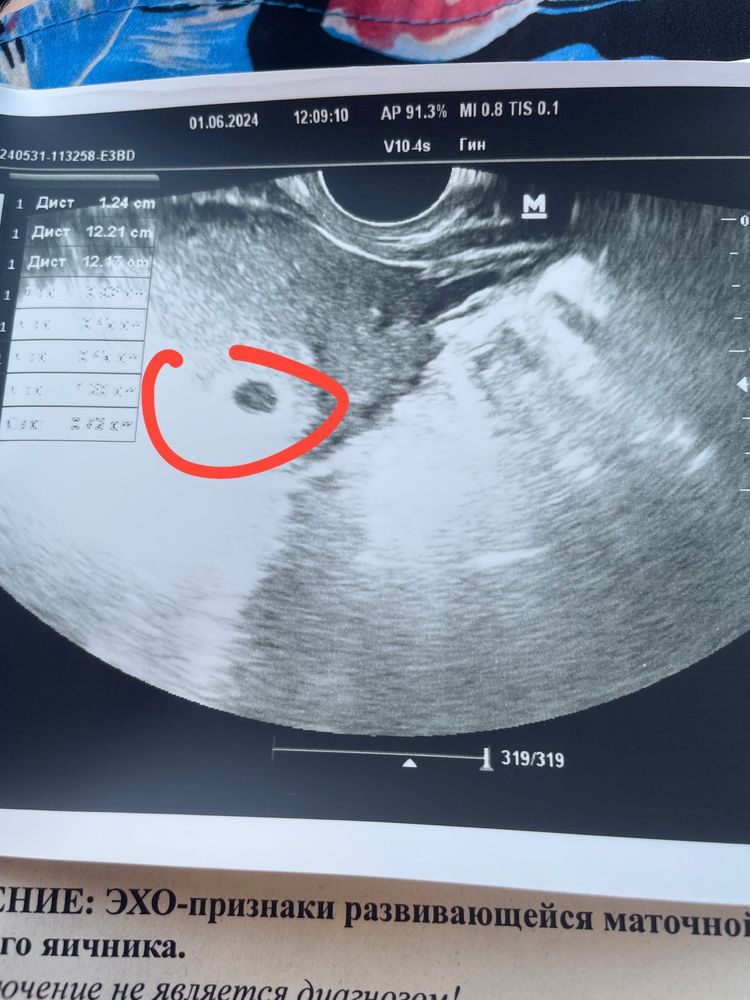

Анна Ян, Изображение

01.06.2024

Анна Ян, через 2 недели сказали прийти теперь

Автор, сердечко будет слышно 🥹🥹самый прекрасный звук....